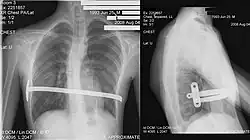

![]() X-Ray of a 15-year-old male after undergoing the procedure | |

The Nuss procedure is a minimally invasive procedure, invented in 1987 by Dr. Donald Nuss and his colleagues, Dr. Daniel Croitoru and Dr. Robert Kelly, for treating pectus excavatum.[1][2][3] He developed it at Children's Hospital of The King's Daughters, in Norfolk, Virginia. The operation typically takes approximately two hours.[4]: 1277 [5]

Through two small incisions in the side of the chest, an introducer is pushed along posterior to the sternum and ribs, and anterior to the heart and lungs. Then a concave stainless steel bar is slipped under the sternum, through the incisions in the side of the chest. A third, smaller incision is made to insert a thoracoscope (small camera) used to help guide the bar. Taller patients, older patients, or patients requiring extensive correction may receive two or more bars. All bars may be placed through two incisions or additional incisions may be made. The bar is then flipped, and the sternum pops out. To support the bar and keep it in place, a metal plate called a stabilizer may be inserted with the bar on one side of the torso. PDS sutures may also be used in addition to the stabilizer. The stabilizer fits around the bar and into the ribcage. The bar and stabilizer are secured with sutures that dissolve in about six months.

Bar removal

After a period of two to four years,[6]: 343 the surgical stainless steel bar is removed from the patient's chest. This procedure lasts approximately ninety minutes. The length of time that the patient stays at the hospital following the bar removal procedure varies, depending on the amount of new bone growth surrounding the bar. Accordingly, the length of time may range from a few hours to several days, or up to one week.